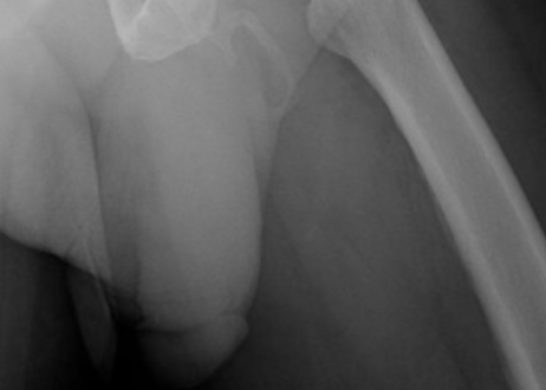

14 agosto, 2019 Gracias a caída hombre descubrió que su pene se estaba convirtiendo en hueso Luego de sufrir una caída, se descubrió la rarísima condición del hombre, a través de una radiografía que mostró su pene convirtiéndose en hueso.